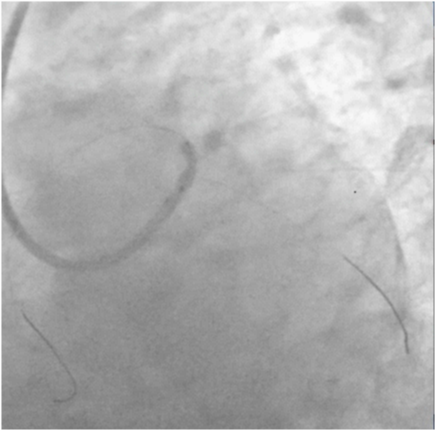

The patient was wheeled into the catch lab after pre-loading with 60mg Prasugrel and 300mg of Aspirin. He received 7,500units of unfractionated heparin and underwent coronary angiography from the right femoral route, which revealed 70% distal left main (LM) stenosis, and 70-80% ostial blocks of the left anterior descending (LAD) and left circumflex (LCX) arteries (Figures 2 & 3), (Video 1).The right coronary artery had a 50% stenosis at mid level (Figure 4). The patient was continuing to have chest pain despite prior administration of intra-venous morphine in the ER. He however was in a position to give informed consent for primary percutaneous intervention (PCI) subsequent to explaining that PCI would be a viable alternative keeping in view the urgency of intervention in his condition.

Figure 2 Coronary angiogram in right anterior oblique caudal view showing tight distal left main and ostial left anterior descending coronary arteries stenosis.

Figure 3 Spider view showing tight distal left main, ostial left anterior descending and ostial left circumflex arteries stenosis.